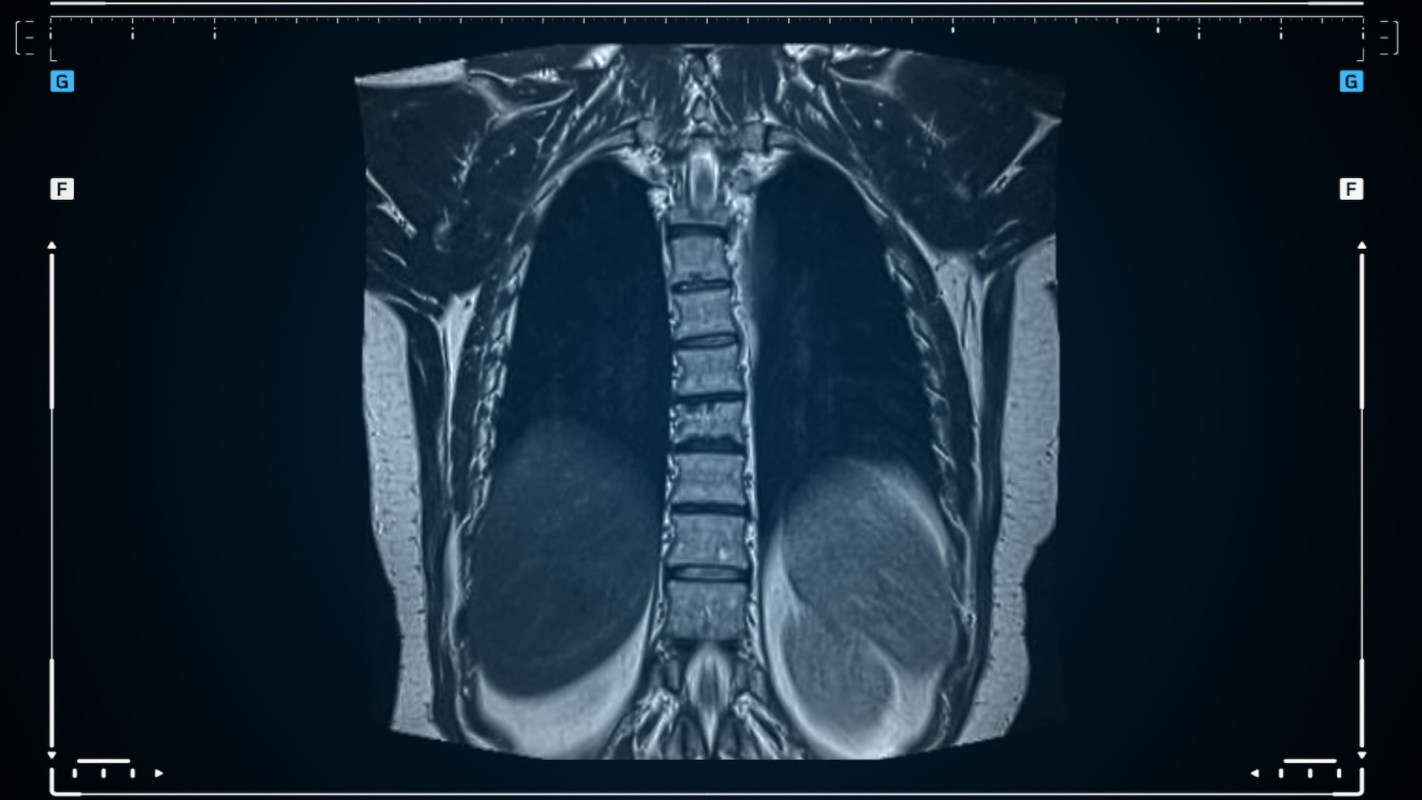

It's been established that microplastics have detrimental effects on lung health, inducing inflammation, oxidative stress, and impaired lung function. However, scientists at the MedUni Vienna have made an important discovery linking microplastics to lung cancer.

Their study, published in the Journal of Hazardous Materials, examined the interaction of polystyrene micro- and nanoplastics with various lung cells. Polystyrene is a common plastic often used in its foam form for take-out containers or food packaging, as seen in the meat aisle of many grocery stores.

The scientists found that after exposure to microplastic particles, healthy lung cells showed "increased cell migration, DNA damage, oxidative stress and the activation of signalling pathways that promote cell growth and survival — all processes that are considered early indicators of cancer development," per the university release.